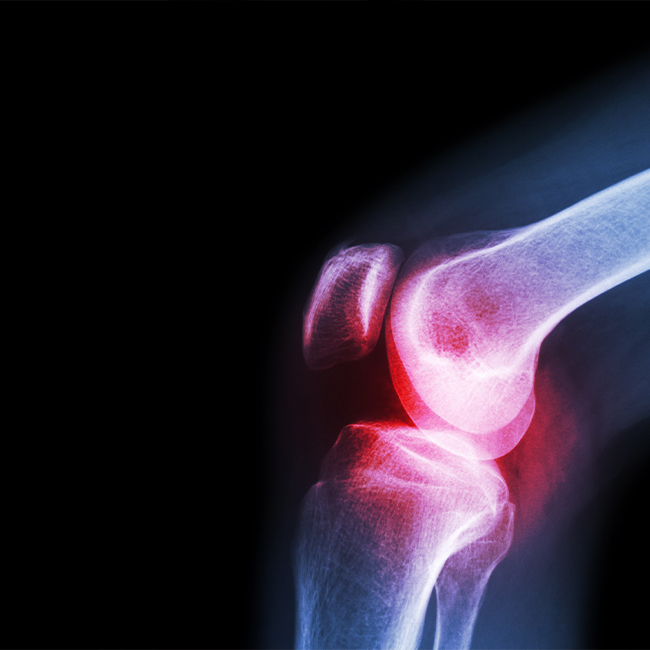

The diagnosis and treatment of inflammatory rheumatic diseases such as spondyloarthropathies (inflammatory spinal rheumatism), rheumatoid arthritis, connective tissue disorders (systemic lupus erythematosus, Sjögren syndrome, scleroderma, etc.), gout, vasculitis (diseases that cause inflammation of blood vessel), Familial Mediterranean fever, Behçet's disease and non-inflammatory rheumatism diseases such as osteoarthritis (degenerative joint disease), osteoporosis and fibromyalgia are carried out.

Patients are assessed through a holistic approach regarding medical conditions and inflammatory rheumatoid diseases such as spondyloarthropathy (rheumatoid spinal inflammation), rheumatoid arthritis, connective tissue diseases (systemic lupus erythematosis, Sjorgen’s syndrome, scleroderma), gout disease, vasculitis (diseases which cause vascular inflammation)

Familial Mediterranean Fever, Behçet’s disease and non-inflammatory rheumatoid diseases such as osteoarthritis (degenerative joint disease), osteoporosis, fibromyalgia are diagnosed and treated in Rheumatology Division.